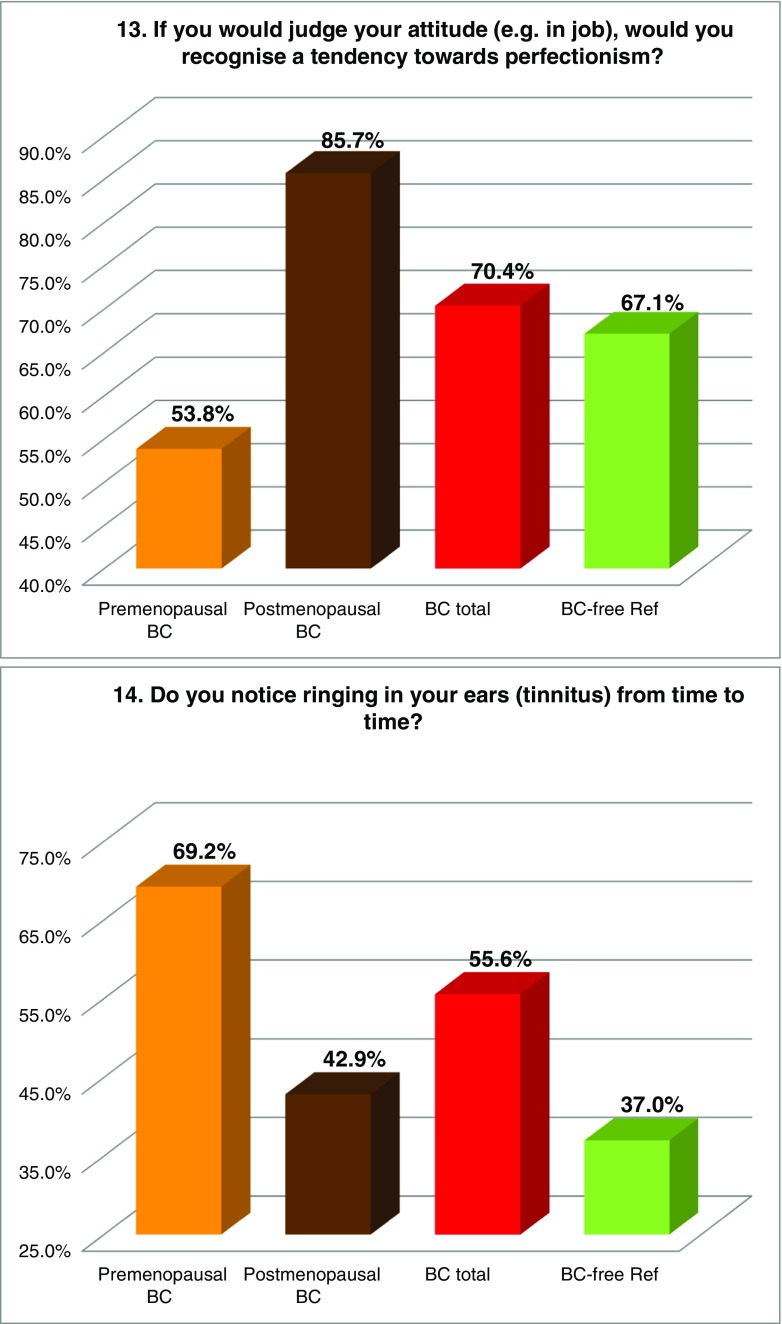

FS prevalence evaluated by individual symptoms

Figure 2 summarises the prevalence of individual “Flammer Syndrome” symptoms (1–15) in two main groups of comparison—“BC total” patients versus the reference group of “BC-free” individuals as well as in individual subgroups of BC patients subdivided according to their menopausal status. Higher prevalence in “BC total” (marked in red) has been demonstrated for all 15 symptoms investigated in this study. Statistical significance has been recorded for symptoms 1 (cold extremities), 2 (feeling cold), 5 (prolonged sleep onset), 7 (headache), 8 (accompanying symptoms), 9 (drug sensitivity) and 11 (smell perception); corresponding p values are provided in Table 3. Although being statistically non-significant (p = 0.103), a substantially greater prevalence has been demonstrated for symptom 6: “no feeling of thirst and drinking too little” the BC patients, in general, have demonstrated two times more frequently compared to the disease-free reference group; for the postmenopausal BC, this difference was even more pronounced. Also, the appearance of tinnitus (symptom 14), although being statistically non-significant (p = 0.095), was evidently more frequent in BC, particularly in the premenopausal subgroup demonstrating about two times higher prevalence compared to the disease-free reference group. Symptom 3 (low blood pressure) was more specific for the premenopausal BC demonstrating 22% higher prevalence against the disease-free reference group. In contrast, symptom 12 (low body weight in early adulthood) was more specific for postmenopausal BC. A slightly higher prevalence was demonstrated for symptom 4 (dizziness) in BC. Strong plurality has been demonstrated amongst the BC subgroups for the following three symptoms: 10 (pain, more specific for the postmenopausal BC), 13 (perfectionism, more specific for the postmenopausal BC) and 15 (skin blotches in stress, more specific for the premenopausal BC) as summarised in Table 3.

Fig. 2.

Evaluation of the prevalence of individual symptoms (1–15) of the “Flammer Syndrome” phenotype in two groups of comparison: “Breast cancer diseased” (BC total) versus “Breast cancer-free” reference (BC-free Ref) groups. Therein, the entire breast cancer patient pool (“BC total”) has been additionally analysed in subgroups stratified according to the menopausal status of the patients. For more details regarding the patient’s recruitment and stratification, see “Materials and methods” section. The prevalence in each individual group is presented by percentage of individuals who have responded to the corresponding question with “frequently” and “sometimes” pooled together. Responders answering with “I do not know” have been excluded from the overall numbers/calculations. Question-specific notes: question 6—the ratio between “I do not feel thirsty and drink little” and “I feel much thirsty and drink a lot” has been calculated and expressed as X times; question 12—answers “very slim” and “slim” are pooled together and presented in percentage

Table 3.

Symptoms of the “Flammer Syndrome” recorded in “Metastatic breast cancer patients” versus “Breast cancer-free individuals” groups of comparison

The table summarises the results demonstrated in Fig. 2; the following system is employed: “+” means higher prevalence of the corresponding symptom (above the lowest average of the groups of comparison); “−“ means lower prevalence of the corresponding symptom (lowest average and below it); “++“ means values sufficiently over the highest average. All 15 symptoms demonstrate increased prevalence in BC total versus BC-free. The level of significance is noted: p values below 0.05 are considered statistically significant and marked in red colour (symptoms 1, 2, 5, 7, 8, 9, 11). Thirteen symptoms united within the green-marked cluster demonstrate the prevalence ultimately increased in BC total as well as BC subgroups. Although the prevalence of symptoms 13 and 15 (yellow-marked cluster) is slightly increased in “BC total” compared to “BC-free,” it varies in BC subgroups demonstrating a particularly strong plurality amongst the patients with the metastatic BC investigated in the current study

The meaning of individual FS symptoms specifically for the BC patient cohort has been discussed in detail in the recently published article “Breast Cancer and Flammer Syndrome: Any Symptoms in Common for Prediction, Prevention and Personalised Medical Approach?” [28]. Current chapter emphasises a particular relevance of the FS symptoms for the metastatic disease in the BC patient cohort: all 15 symptoms demonstrate the prevalence in the metastatic BC versus BC-free reference group with a statistical significance (p ≤ 0.05) for seven symptoms as summarised in Table 3. Other symptoms, even being statistically non-significantly prevalent within this study, can be of great importance for the BC pathology and metastatic disease. Hence, symptom 3 (low blood pressure, p = 0.127) is particularly relevant for the premenopausal subgroup and may strongly contribute the cardio-vascular component characteristic for the FS as explained above. Another example is the following: symptom 4 (dizziness, p = 0.762) has been described earlier as being permanently present and stepwise worsening in BC followed by metastasis in the brain [20, 33]. Finally, the normal feeling of thirst (symptom 6, p = 0.103) is extremely important and if diminished (here two times in BC versus BC-free) plays a crucial role in the body dehydration and BC development [20].